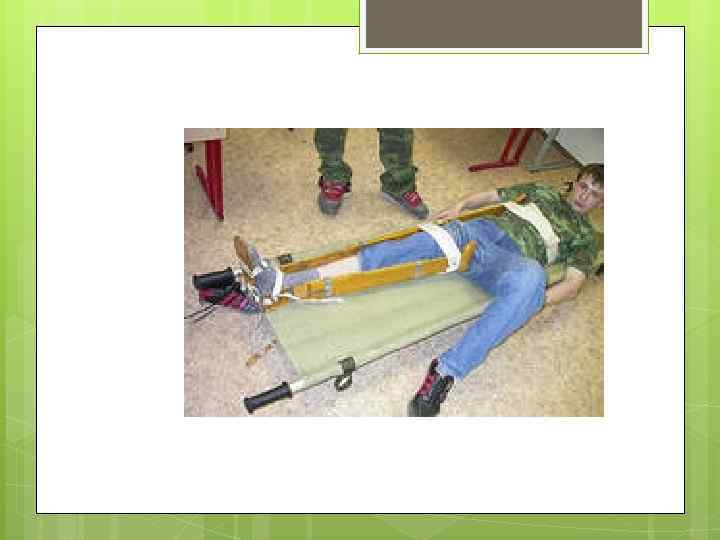

При оказании первой медицинской помощи пораженному в состоянии шока необходимо остановить опасное для жизни кровотечение, ввести шприц-тюбиком противоболевое средство, защитить от холода, при наличии переломов провести транспортную иммобилизацию. В тех случаях, когда шприц – тюбик с противоболевым средством отсутствует, пораженному в состоянии шока, если нет проникающего ранения живота, можно дать алкоголь (вино, водку, разведенный спирт), горячий кофе, чай. Пораженного укрывают одеялом и как можно быстрее бережно на носилках транспортируют в медицинское учреждение.

При оказании первой медицинской помощи пораженному в состоянии шока необходимо остановить опасное для жизни кровотечение, ввести шприц-тюбиком противоболевое средство, защитить от холода, при наличии переломов провести транспортную иммобилизацию. В тех случаях, когда шприц – тюбик с противоболевым средством отсутствует, пораженному в состоянии шока, если нет проникающего ранения живота, можно дать алкоголь (вино, водку, разведенный спирт), горячий кофе, чай. Пораженного укрывают одеялом и как можно быстрее бережно на носилках транспортируют в медицинское учреждение.